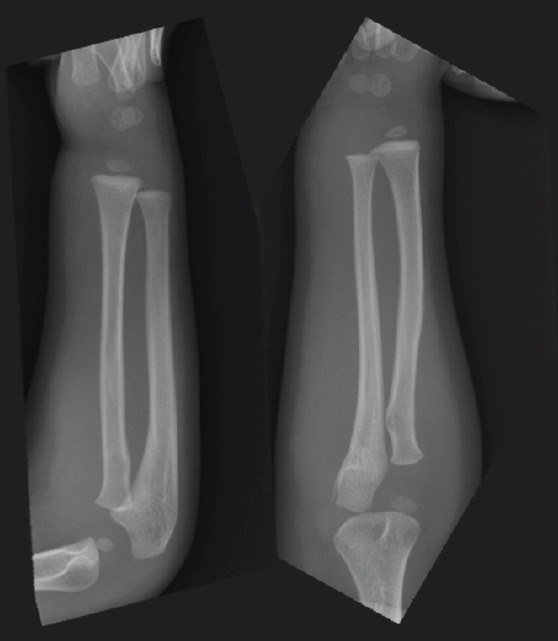

Case report: A 2-year-old boy had right upper extremity pain and paralysis after falling from a chair. He had no family history of congenital hemorrhagic diseases or anticoagulant medications. His right distal forearm to hand was congested with a clear borderline to the proximal forearm. It was unable to detect any fractures in the X-rays. We diagnosed him with AFCS and performed a fasciotomy that showed a developing hematoma around the carpal tunnel. Two years after surgery, he had no signs of neurological defect in the upper extremity.